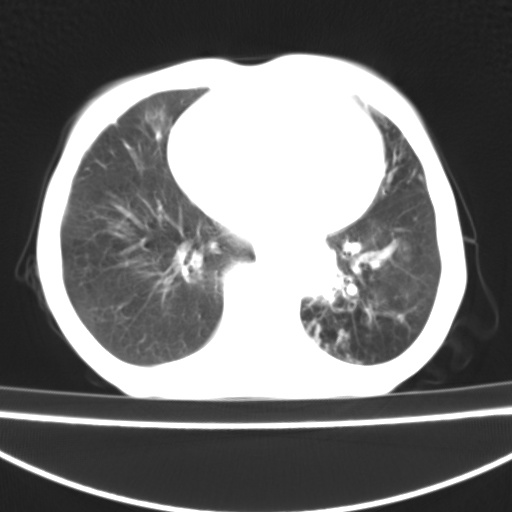

患者 女 67岁,反复咳嗽咳痰2年,加重伴喘及双下肢浮肿1月

陈旧性肺结核、慢性支气管炎、支气管扩张症、肺心症、肺动脉高压。

诸大血管及f肺门血管增粗迂曲.左下肺多发薄壁空腔影.部分非也透亮度增高.薄曾扫描可区分肺气肿类型.考虑1.慢性支气管炎 2.左下肺支气管扩张 3.肺气肿 4 肺动脉高压5.是否有先心病病史

考虑1.慢性支气管炎 2.左下肺支气管扩张 3.肺气肿 4 肺动脉高压

慢支炎、肺气肿、双肺感染、左下囊状支扩。

慢支、肺气肿、肺动脉高压;左下肺囊状支扩并粘液栓形成。